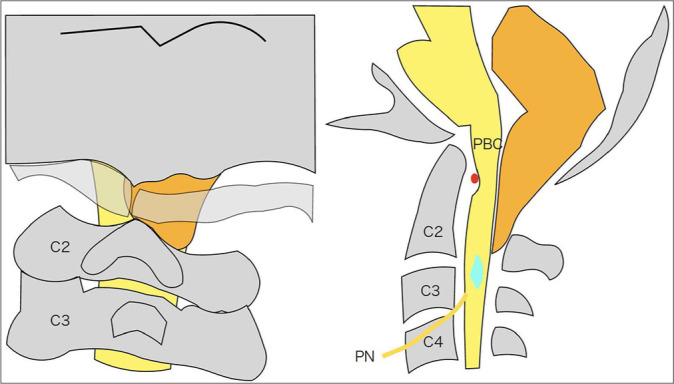

背景:咳嗽性晕厥、中枢性睡眠呼吸暂停(CSA)和伴有寰椎同化的Chiari 1型畸形(CM1)在成人中非常罕见。病例描述:一名48岁男性出租车司机晕倒。他的神经系统是完整的,但经多面体图检测,轻度睡眠呼吸暂停呈阳性。磁共振成像诊断为CM1伴脊髓空洞和寰枕。患者在7年后接受了大枕骨孔减压/C1椎板切除术,并保持完整。结论:1例48岁男性晕厥后出现咳嗽性晕厥、CSA和CM1;在枕骨大孔减压/C1椎板切除术后,患者在接下来的7年中保持神经系统稳定。

Case description: A 48-year-old male taxi driver fainted. He was neurologically intact, but tested positive for mild sleep apnea confirmed by a polysonogram. The magnetic resonance imaging diagnosed a CM1 with syringomyelia and atlas occipitalization. The patient underwent an uneventful foramen magnum decompression/C1 laminectomy and remained intact 7 years later.